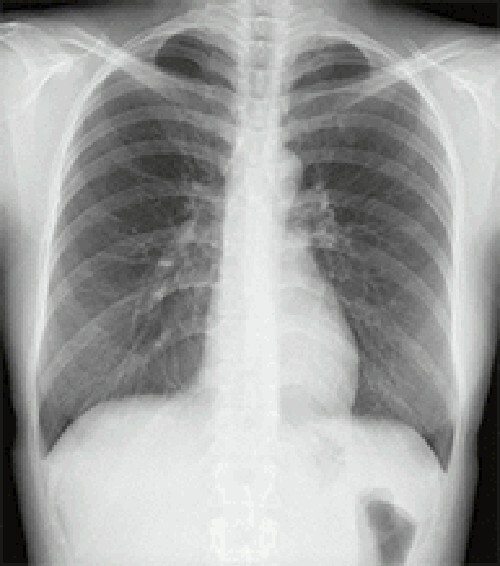

マルチスライスCTスキャナは寝台に横になるだけで頭部・胸部・腹部など体内を断層(輪切り)で撮影できる検査です。

従来装置(64列)に比べて高速、高精度の撮影が可能なだけでなく、患者様の体型に合わせて線量を可変できるため適切なX線量で検査できます。

診断や治療のために骨や血管の3D(立体的な三次元画像)を作成することもできます。